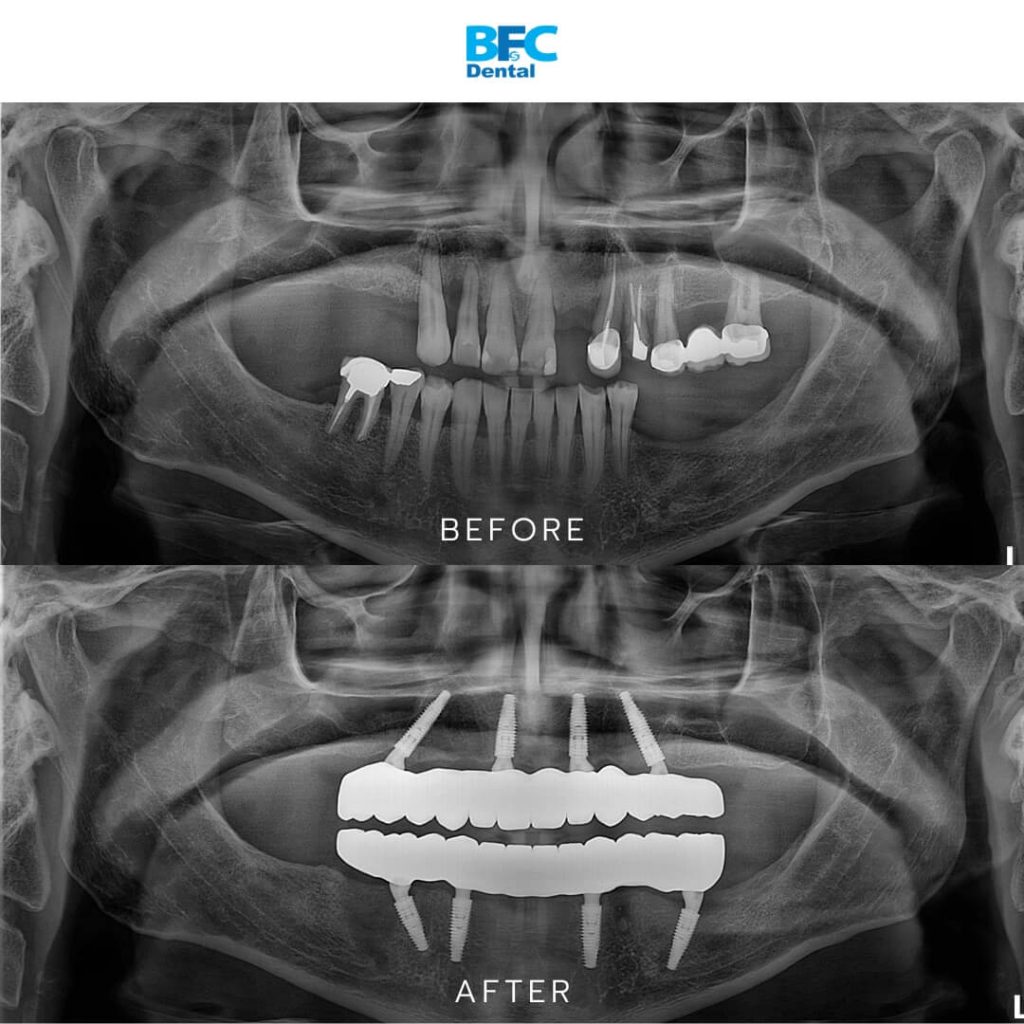

สำหรับผู้ที่สูญเสียฟันแท้หลายซี่หรือทั้งปาก รากเทียมทั้งปาก (Full Mouth Dental Implants) ถือเป็นทางออกที่มีประสิทธิภาพในการคืนฟันและรอยยิ้มมั่นใจให้กลับมาอีกครั้ง โดยการทำรากเทียมทั้งปากคือการฝังรากเทียมหลายตัวลงในขากรรไกรเพื่อรองรับสะพานฟันแบบติดแน่น โดยไม่จำเป็นต้องฝังรากเทียมให้ครบทุกซี่ฟันที่หายไป เช่น เคสนี้ใช้รากเทียมเพียงขากรรไกรละ 4 ตัว (All-on-4) รองรับสะพานฟันทั้งแถว โดยฟันปลอมติดแน่นบนรากเทียมจะทำหน้าที่เสมือนฟันแท้ นั่นหมายถึงคนไข้จะสามารถกลับมาเคี้ยวอาหารได้ตามปกติ พูดออกเสียงได้ชัดเจน และยิ้มได้อย่างมั่นใจโดยที่ฟันปลอมไม่เลื่อนหลุด

- ฝังรากฟันเทียม 4 ตัวในขากรรไกรบน และ 4 ตัวในขากรรไกรล่าง: หลังจากถอนฟัน ทันตแพทย์ฝังรากเทียม 4 ตัวต่อขากรรไกร

การเปลี่ยนแปลงอย่างชัดเจน: ฟันชุดใหม่ที่ได้จากการทำรากเทียมทั้งปากนั้นเรียงตัวสวยแนบกับเหงือก การสบฟันกลับมาเป็นปกติ คนไข้สามารถบดเคี้ยวอาหารได้ดีขึ้นมาก และใบหน้าก็ดูเต็มอิ่มขึ้น นอกจากนี้ฟันปลอมแบบติดแน่นที่ยึดกับรากเทียมยังไม่ขยับหรือหลวม เวลายิ้มก็เผยให้เห็นฟันสีสวยเป็นธรรมชาติที่กลมกลืนกับเหงือกจริง ช่วยเสริมให้รอยยิ้มดูเป็นธรรมชาติและสวยงามยิ่งขึ้น